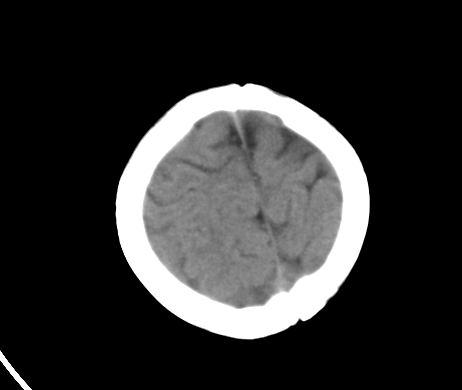

标题: PED1850:男 2岁 头部外伤1天,有事吗?

男 2岁 头部外伤1天,有事吗?科里意见不一 骨窗 没事,未上传

脑先天发月不对称

未见与外伤有关病变;脑白质的比例较少,有发育异常吗?